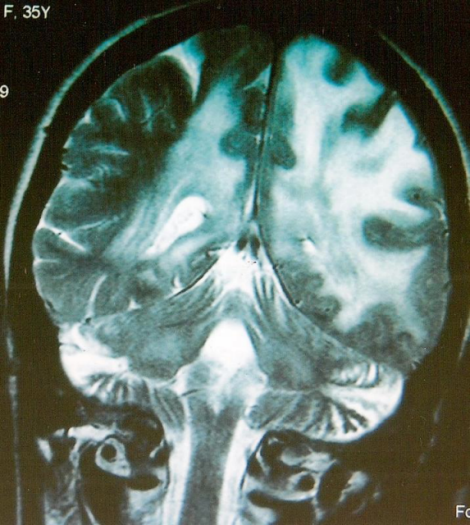

A 35 year old Kashmiri female had presented with history of increased talkativeness, quarrelsome attitude, forgetfulness, poor recognition of close relations, social withdrawal, aimless wandering of 3 weeks duration to a local psychiatrist. She had no relief in her symptoms on psychiatric treatment. She was brought to medical emergency room of Govt. S.M.H.S Hospital Srinagar, an associated hospital of the Govt. Medical College Srinagar, Kashmir, when her husband noticed weakness of the right side of the body with deviation of face to one side of 3 days duration. Soon after admission in the emergency room she became drowsy and had incontinence of urine without any convulsions. There was no history of fever or rash, or bleeding from any site. She was nondiabetic with no significant medical history in the past. On examination the patient was drowsy but arousable, however she was not oriented to time, place or person. She had no jaundice or lymphadenopathy. Her systemic examination was normal. The neurological examination revealed positive neck stiffness, right facial palsy and right hemiplegia. Her right side plantar was upgoing. She had right side papilloedema on fundoscopic examination. On evaluation she was found to have leukocytosis (11200) with high erythrocyte sedimentation rate (60 min first hour). Her liver and renal function tests, serum calcium and phosphorous were normal. ECG and x-ray chest revealed no abnormality. HIV serology was negative. CT scan of the head revealed white matter edema of the left parieto-occipital region with mass effect on the left ventricle with midline shift suggestive of venous thrombosis. Contrast CT of the head showed enhancement of these lesions suggestive of demyelination (Figure 1 [Fig. 1]). Contrast MRI of the brain showed extensive vasogenic edema in periventricular white matter, predominantly in the left parieto-occipital region with hyperintense signal in ventral pons and cerebral peduncle (along the descending tracts) with enlarged left cerebral peduncles with mass effect on the left lateral ventricle suggestive of a tumefactive demyelination (Figure 2 [Fig. 2]). She was given decongestive therapy with intravenous Mannitol and lumbar puncture was done very carefully. Cerebrospinal fluid (CSF) analysis revealed a total leucocyte count of 210 cells with 85% lymphocytes, 15% neutrophils, CSF proteins 542 mg/dl, sugar 28 mg/dl, adenosine deaminase (ADA) levels were 27 IU (normal <10), Gram stain and India ink were negative, acid-fast bacteria (AFB) stain was negative. TB polymerase chainreaction (PCR) was positive, venereal disease research laboratory (VDRL) was negative, CSF culture for mycobacterium tuberculosis was positive. On the basis of these findings a 4-drug regimen of antitubercular treatment (ATT) (Tab. INH 300 mg, Cap. Rifampcin 600 mg, Tab. Ethambutol 800 mg, Tab. Pyrazinamide 1.5 g and Tab. Pyridoxine 60 mg) was started. She was given Inj. Methylprednisolone 1 g I/V once daily for 5 days followed by oral steroids (Tab. Prednisolone 40 mg daily). Oral steroids were tapered over the next four weeks and ATT was continued. The patient had progressive improvement in 4 weeks time. On discharge she was conscious, oriented to time place and person and had power of grade V in all four limbs. Repeat CT done after 4 weeks showed marked regression of edema and repeat MRI done after three months of ATT showed few post ADEM residual demyelinating lesions (Figure 3 [Fig. 3]). The patient is fine now and is following our clinic for the last one year now.

Figure 2: MRI before treatment